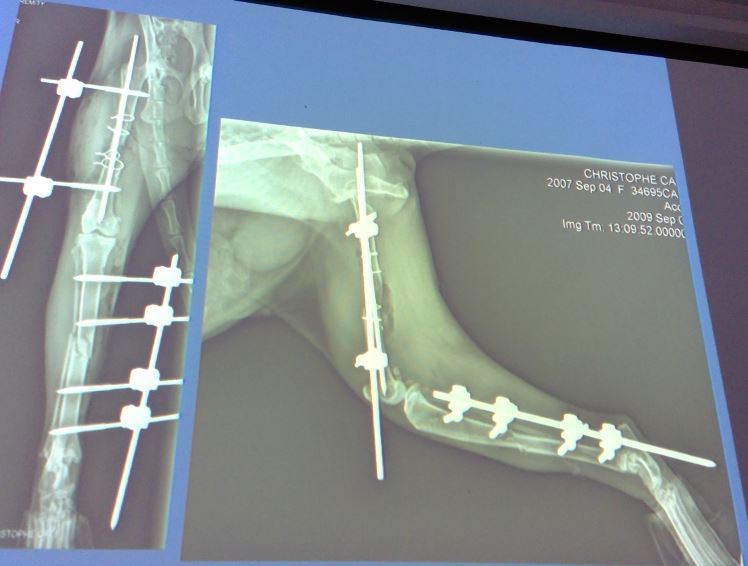

18 month old M pitbull, 22kg

A

Simple transverse fracture of the distal diaphysis of the femur

Fx score= 10

Repair= ESF + IM pin

IM pin + cerclage wire C/O’d on transverse fx